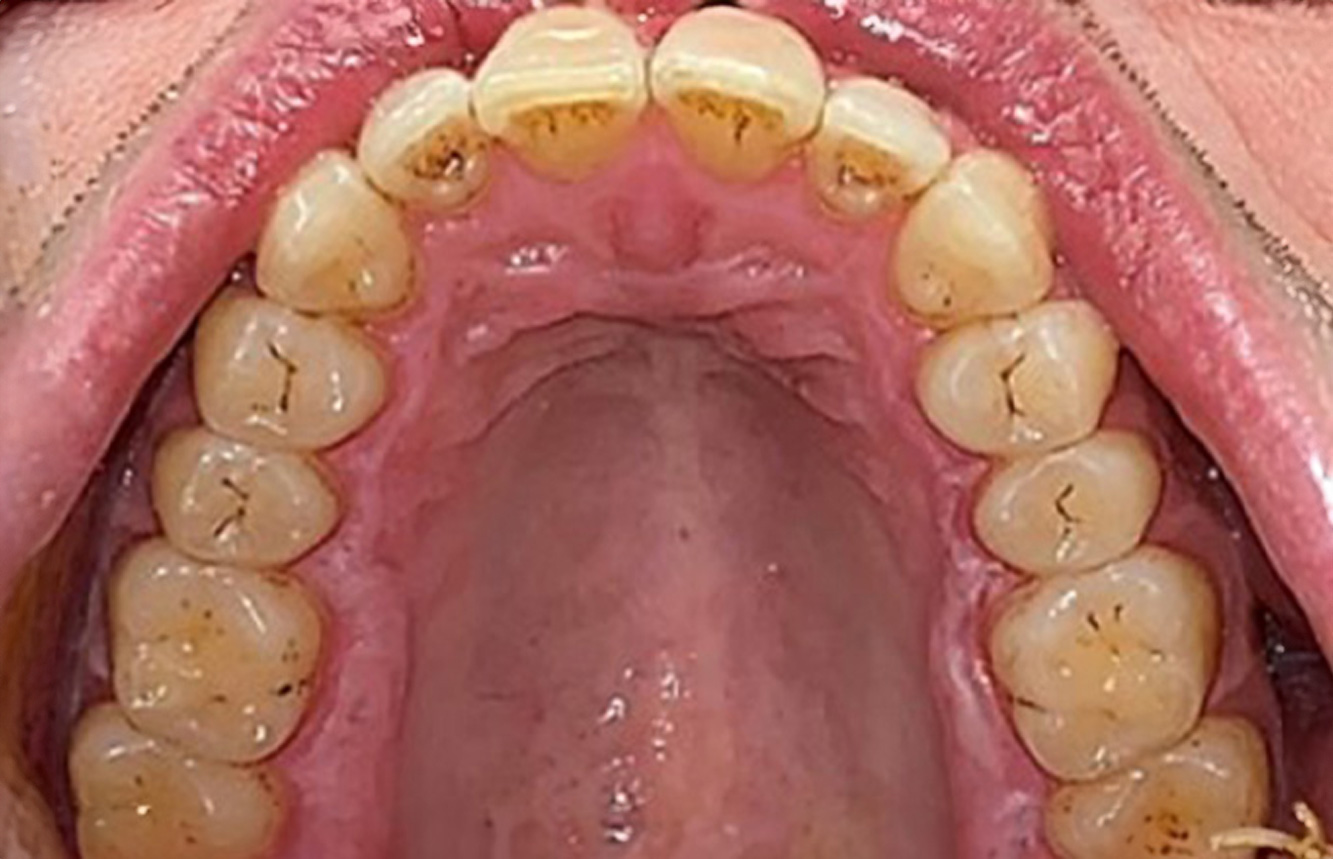

Un pacient în vârstă de 71 de ani, cu transplant de rinichi și istoric de hipertonie (hipertensiune arterială) se prezintă în cabinet. Din cauza istoricului său medical, este necesară o medicație pe termen lung cu ciclosporină, pentru a suprima sistemul imunitar, precum și amlodipină pentru a reduce tensiunea arterială. Pacientul raportează, de asemenea, gingii sensibile și sângerânde. Din punct de vedere al sănătății orale, pacientul are lucrări dentare, o edentație de opt dinți, creștere gingivală pronunțată și parodontoză de gradul B, stadiul II, cu pungi active și carii radiculare inițiale la dintele 22. Evaluarea riscului de carie determină un risc moderat de carie (API 60). Se pot stabili următoarele recomandări de tratament pentru ședința de profilaxie. mai multe